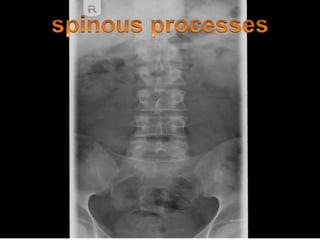

Test for Spinal Problems

Straight Leg Raising (Lasègue’s Test). Perform

this test when the patient complains of low

back pain that radiates down the leg (sciatica).

This test checks for a herniated nucleus

pulposus. Ask the patient to lie flat and raise

the affected leg to the point of pain

(Fig.20.11).Pain and sciatica that intensify with

dorsiflexion        of          the          foot.